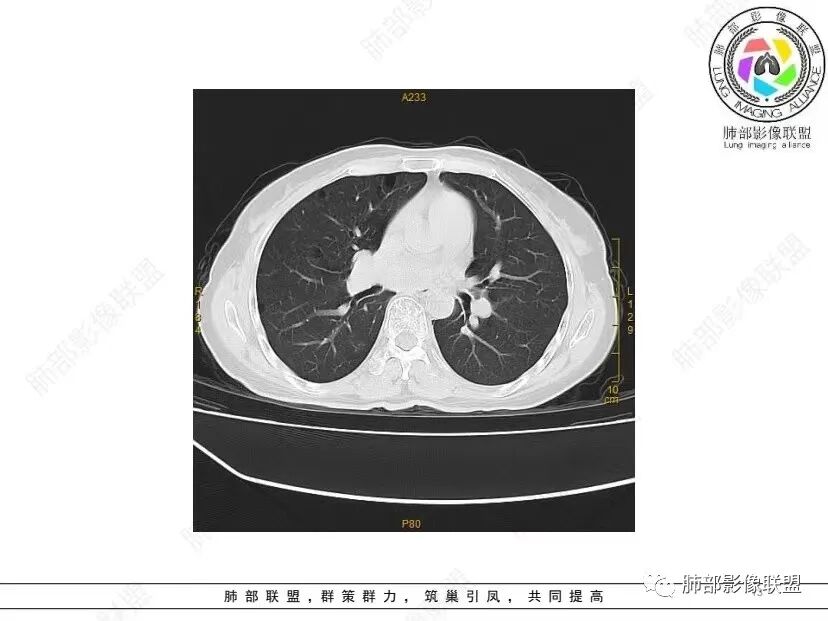

秦化君: 晨读 双肺不均匀散在多发囊状影,大小不等,部分囊形态欠规整,壁薄均匀,部分囊胸膜下平行。双肺少许斑片状磨玻璃影,边缘模糊。考虑BHD综合征。鉴别PCP,LIP。

红日初升: 中年女性,双肺多发气囊,背景干净,大小不一,下肺韧带旁较大,考虑BHD,鉴别LIP、LAM

玫: 晨读:女,49岁,双肺散在多发囊性病灶影,薄壁,部分层面病灶形态欠规整,右肺下叶少许磨玻璃影,边缘模糊,考虑LIP,鉴别BHD。

宇宙: 中年女性,两肺多发大小不等薄壁囊状影,两肺纵膈胸膜下分布明显,考虑BHD,鉴别LAM

放射线 (王秀仙): 双肺多发囊状影,大小不等,部分囊壁呈磨玻璃样,另双肺见斑片状磨玻璃影,边缘模糊。女性,考虑LIP,鉴别BHD

段建民: 双肺多发囊状影,多成圆形或三角形,囊壁薄且均匀,正常肺野内透过度尚可。双肺多发囊状影的鉴别,中心肺气肿,间隔旁肺气肿,PJP,支气管扩张,囊肿,支气管肺发育异常;LAM LIP PLCH BHD;囊腔腺癌,转移瘤,血播金葡菌……

本病例首先考虑BHD。

良孑: 两肺多发含气囊腔,大小不等,囊周见血管伴行,首选BHD,建议查双肾情况,鉴别Lam

这个病例目前影像特点,多囊,囊主要位于下肺,胸膜下及小叶核心为主

伴随少许索条,而且这些病灶与囊不一定有相关性

囊的分布,PLCH基本可以排除

囊壁薄且均匀,光滑,形态规则,基本除外恶性

单纯囊,无斑片及其他实性病灶,感染不支持,可能的是:LAM、BHD、LIP

从囊的分布、大小,BHD可能性可能大一些,但是LIP、LAM都可以这样表现,具体诊断应该是这三种之一,影像缩小到这里我觉得就差不多了,结合临床考虑就行,不支持靠影像强下结论。